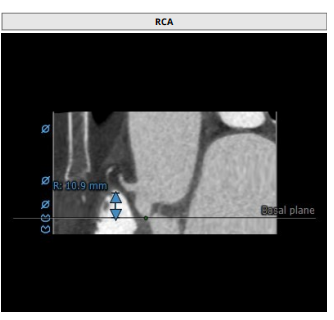

瓣环:16.9mm,左室流出道:16.7mm

瓣叶增厚 右冠高度:10.9mm,左冠高度:9.5mm